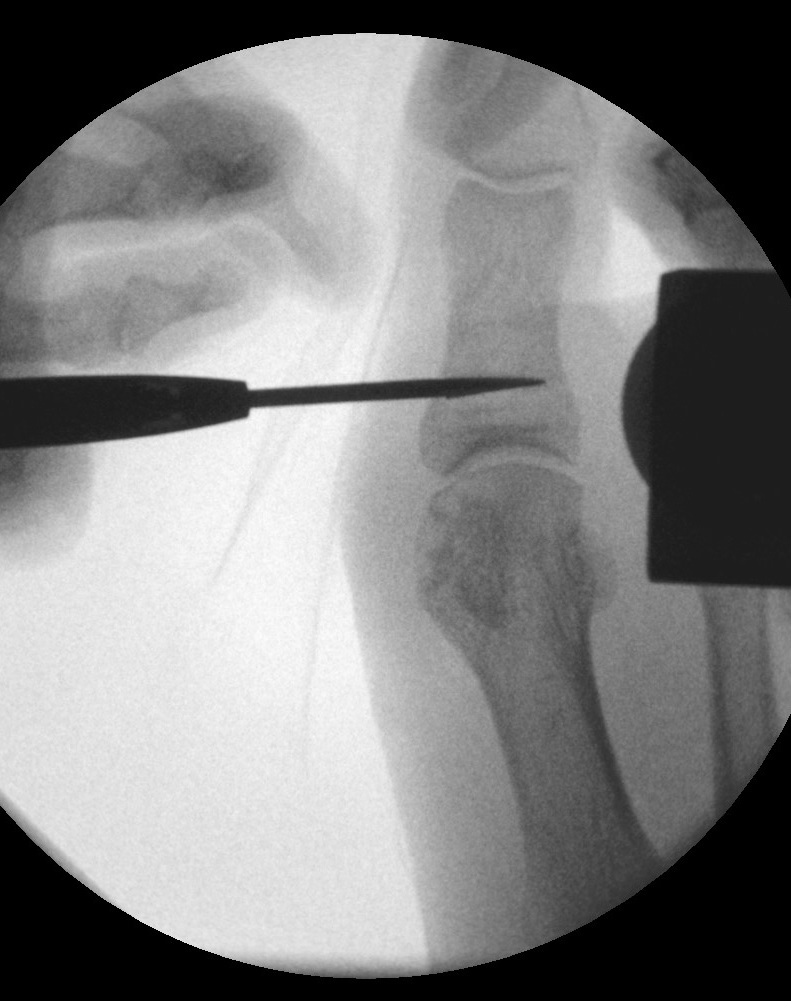

Operationstechnik (Text und Fotos)

Zum Lesen der Bildbeschreibung und zur Vollansicht bitte die Bilder anklicken. Bilder: Dr. med. Gerhard Kaufmann.